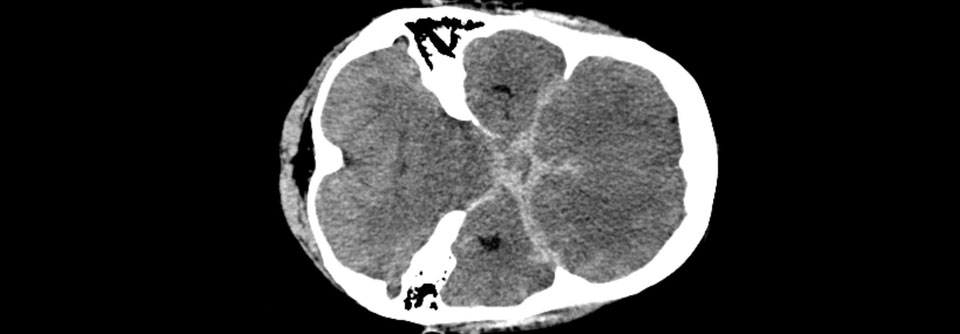

Methode der ersten Wahl bei Verdacht auf eine SAB ist aufgrund der Schnelligkeit und breiten Verfügbarkeit die native craniale Computertomographie (cCT):

• Nachweis von subarachnoidalem Blut (hyperdens) – insbesondere in basalen Zisternen und Sulci

• hohe Sensitivität von 95 % bei Akutereignis (bei subakuten Blutungen besser MRT)

• Nachweis weiterer möglicher Befunde (z.B. andere Blutungen, beginnender Aufstau der Ventrikel, Hirnödem, ischämische Hirninfarkte)